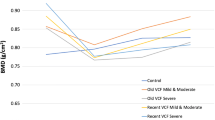

Under the 100 N postero-anterior load, while the stresses were rather similar for the healthy, osteoporotic, and severe osteoporotic cases, the strains were much higher for the latter case (Figs. 4, 5). The posterior structures of L1 vertebra, which consisted of pedicles, laminae, and spinous process, demonstrated higher von Mises stresses and larger magnitude of minimum principal strains than the vertebral body.

While the Young’s modulus differed substantially between the three bone models, the von Mises stress distribution did not differ markedly (< 10 percent). The distribution of the magnitude of minimum principal strains tended to increase when the Young’s modulus was reduced, and it was more predominant to the minimum principal strain than the von Mises stress.

Mean, standard deviation and maximum magnitude of von Mises stress and minimum principal strain are shown in Tables 3 and 4, respectively. For all bone conditions, the maxima occurred at the nearly mid-transverse position of right pedicle. When the yield stress criterion was taken into account (as shown in Table 2), the structures where the maximum von Mises stress exceeded the yield stress criterion were spinous process, vertebral body and pedicles (all models). According to the yield strain criterion (as shown in Table 2), the structures where the maximum magnitude of the minimum principal strain exceeded the yield strain criterion were pedicles (osteoporotic and severe osteoporotic model) and spinous process (only severe osteoporotic model).

This study showed that postero-anterior mobilization in elderly female osteoporotic lumbar vertebral bone can cause fracture of the pedicles and spinous process of lumbar vertebra. Furthermore, the comparison of contour plot between Young’s modulus and both stresses and strains (as shown in Figs. 4, 5) emphasized that the minimum principal strain reflected the dominant difference among different bone densities better than the von Mises stress when the lumbar vertebra is under postero-anterior mobilization. The comparison also showed that the lower moduli area induced the higher strains especially on the spinous process (Fig. 5). Meanwhile, the stress was not altered by the variation of Young’s moduli (Fig. 4).

For the fracture risk, the von Mises stress and minimum principal strain have been widely used as the indicators [12,13,14, 19, 28]. In this study, the yield stress of each part of the lumbar vertebra was adopted from previous study [29]. However, the yield stress for the pedicle was lack. There was only one biomechanical study of the ultimate stress of the posterior part of the adult cadaveric lumbar vertebra [29]. It reported the ultimate stress of the laminae and spinous process. Therefore, we extrapolated the ultimate stress of the pedicle same as the ultimate stress of the laminae based on the similar range of elastic moduli to be a yield stress of pedicle in our study. According to the previous computational studies, the yield criterion of strain was set at -10,000 microstrain [30, 31]. Furthermore, the previous experimental study demonstrated the ultimate strain for trabecular bone under the compression ranged from − 3,000 to − 27,900 microstrain (with an average of − 11,000 microstrain) [32]. In our study, the fracture risk occurred at the pedicles of moderate and severe osteoporotic L1 vertebra and in the spinous process of severe osteoporotic L1 vertebra where lower elastic modulus presented.

Our analysis of the variation of the bone properties demonstrated that only the minimum principal strain reflected the difference among bone properties obviously. Based on the simple equation of stress, stress depends on the geometry and the load application. However, stress would be altered when the material reaches the plastic phase because the material is deformed. The heterogeneity of the material also affects the stress distribution. Furthermore, when the heterogeneous property was considered, notable changes in results are observed. Therefore, the conversion of CT image information (Hounsfield number) of bone to the corresponding bone property (Young’s modulus) is important as the reliability of the simulation results depends on bone property, especially in the case of osteoporotic bones.